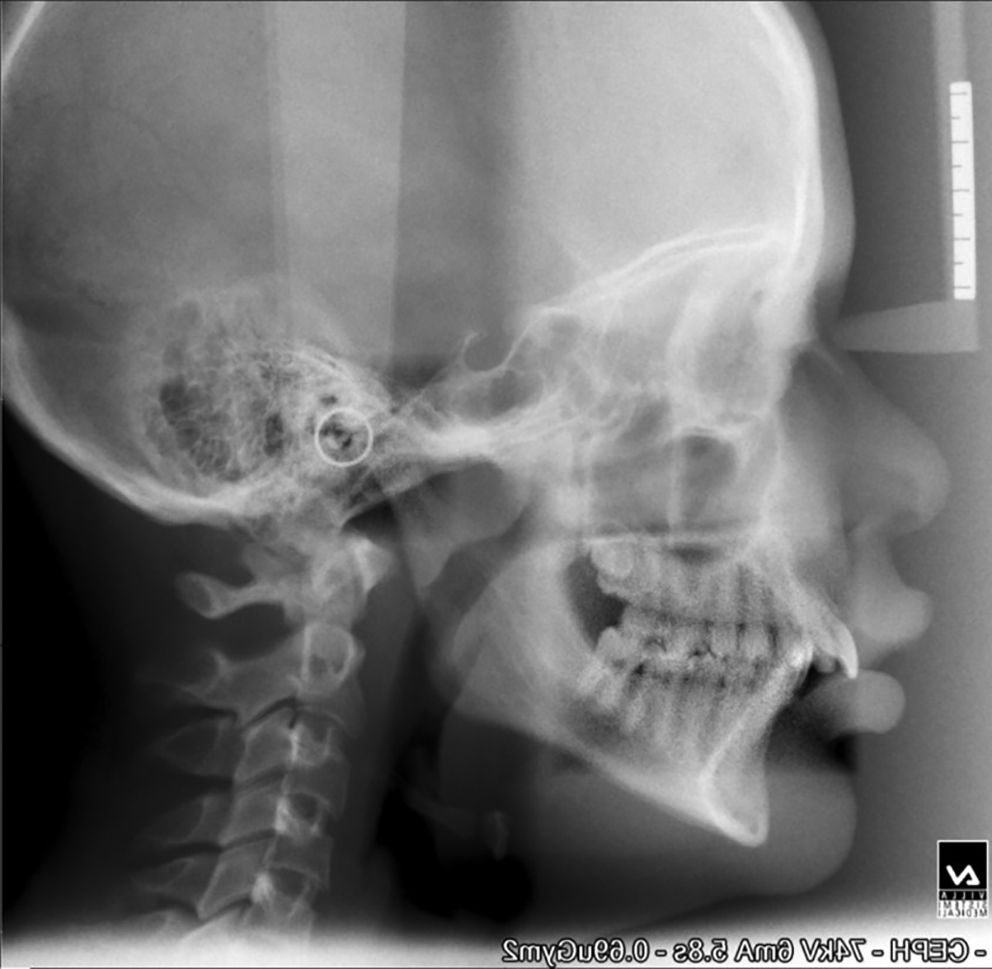

The mean age of the patients at the start of treatment was 12 years. Pre-and post-treatment lateral cephalograms were taken and evaluated for skeletal, dental, and soft tissue changes after wearing a twin block appliance therapy for nine months. Cephalometric changes during treatment are shown in Table 1. Figure 1 shows pre-treatment cephalograms, Figure 2 shows post-treatment cephalograms and Figure 3 shows the superimposition of pre-and post-treatment average digitizations. Twin block appliance wearing resulted in rapid skeletal correction as was evident from a statically significant decrease in angle Point A-Nasion-Point B (ANB), from 7.07±1.98 to 3.33±1.23 degrees (P=0.02); the angle of convexity decreased significantly from 9.87±1.5 to 5.13±1.24 degrees (P=0.01). There was a significant change in Wits appraisal, which decreased from 4.87±0.91 to 3.33±0.72 mm (P=0.04). Angle between Sella-Nasion-Point B (SNB) increased significantly from 74.0±1.46 to 77.9±0.77 degrees (P=0.02). There was a non-significant increase in mandibular length from 86.73±3.34 to 87.8±3.32 mm (P=0.1). The total anterior facial height (increased from 101.73±2.86 to 102.13±2.5 mm, P=0.09) and posterior facial height (increased from 57.27±1.53 to 57.40±1.68 mm, P=0.43) did not show significant changes with no significant increase in Frankfort mandibular angle (FMA increased from 30.73±1.48 to 30.80±1.37 degrees, P=0.67); there were no significant changes in Jarback ratio too (63.73±1.71 to 63.20±1.6, P=0.15); the angle between Sella-Nasion and Gonion-Gnathion (SN-Go-Gn) increased non-significantly from 132.27±2.43 to 132.60±2.29 degrees (P=0.67); the Y-axis increased non-significantly from 56.66±1.75 to 56.86±1.95 degrees (P=0.32). The upper incisor inclination decreased non-significantly from 5.60±1.24 to 4.20±0.86 degrees, (P=0.31) and the lower incisor increased non-significantly from 100.13±2.23 to 101.80±1.37 degrees, (P=0.08). The nasolabial angle increased by 3.8 degrees and the change was statistically significant (P=0.04). The mean pretreatment (stage 0) value of overjet was 9.60±1.35 mm which was statistically significantly (P=0.01) reduced to 3.6±0.91 mm at 9 months (stage IV) of the twin block therapy. The mean overbite before the start of treatment (stage 0) was 6±0.92 mm. This changed to 2.47±0.83 mm at 9 months of twin block therapy. The change was statistically significant (P=0.03).

a4d3a120-46fb-4337-9a75-bc612f9f9675_figure2.gif

Figure 2. Post-treatment cephalogram.